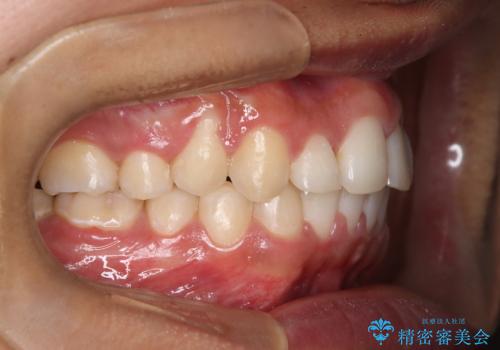

- 咬み合わせの不調和と歯並びのデコボコを主訴にご来院された患者様です。

精密矯正検査の結果、歯を抜かずに非抜歯でワイヤー矯正で治療を行う方針としました。

叢生(歯のデコボコ)の量が多く、加えてディープバイト(過蓋咬合)や重度の捻転も認められたため、リンガルアーチやマイクロインプラントなどの補助装置を併用し、治療を進めました。